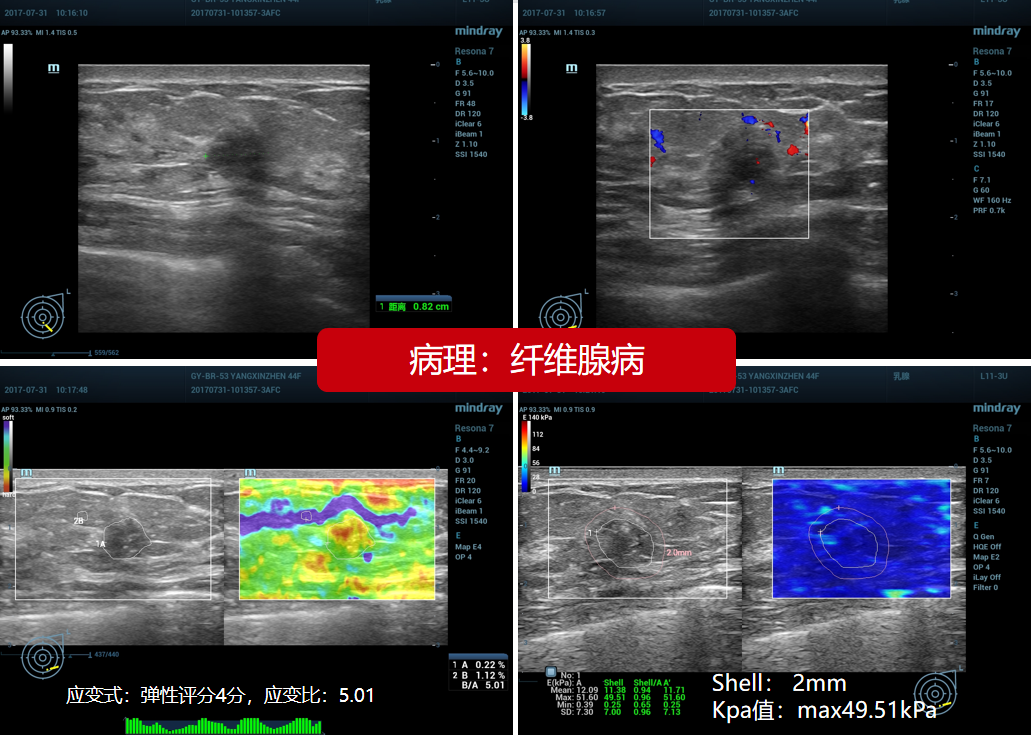

7、乳腺纤维腺病(贵州医科大学附属医院):女,44岁,4a类。